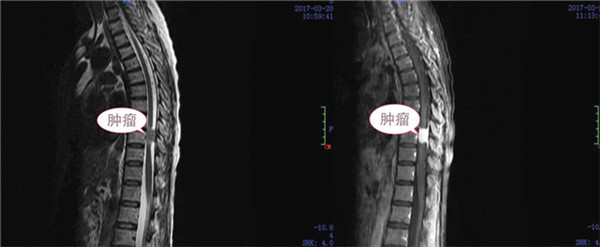

患者于3个月前开始出现双下肢麻木、活动乏力,1周以来呈进行性加重, 并迅速发展至截瘫,大小便失禁。据了解,患者3个月前始已出现身体不适,但未及时汇报,自以为“练功”可以解决问题,而致病情拖延,监狱干警和管理人员及时发现了她的病情,并将她转送广西监狱总医院(南宁茅桥中心医院)就诊,经胸椎核磁共振检查,发现患者胸10水平椎管内占位至椎管狭窄、脊髓严重受压变细,因该院专科治疗水平有限,便紧急联系一附院,外六科主任张高炼教授前往会诊后建议转至一附院。

对于这样一位病情较重而又在服刑期间的特殊患者,一附院开通绿色通道救治及检查,外六科将有限病房腾出一间作为专用,以利患者医疗管理及狱警工作人员值守。针对患者病情,科主任张高炼组织全科进行了疑难病例分析和术前讨论,根据患者症状,结合影像学资料,意见椎管内占位病变为脊膜瘤的可能性较大,因肿瘤造成胸9、10水平脊髓完全受压,有明确手术指征且必须尽快手术切除。经告知患者及家属病情并与监狱领导汇报,大家都期望尽快手术治疗。

术前肿瘤影像